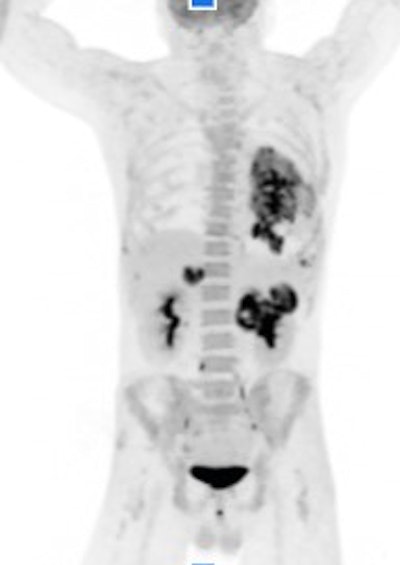

A PET/CT image acquired in 2.5 minutes with Canon's Cartesion Prime PET/CT scanner with deep-learning reconstruction applied. Image courtesy of Canon.

A PET/CT image acquired in 2.5 minutes with Canon's Cartesion Prime PET/CT scanner with deep-learning reconstruction applied. Image courtesy of Canon.Canon is highlighting AiCE DLR reconstruction for Cartesion Prime for both the CT and PET components, and the company is showing PET/CT images acquired in 2.5 minutes, at 30 seconds over five bed positions.